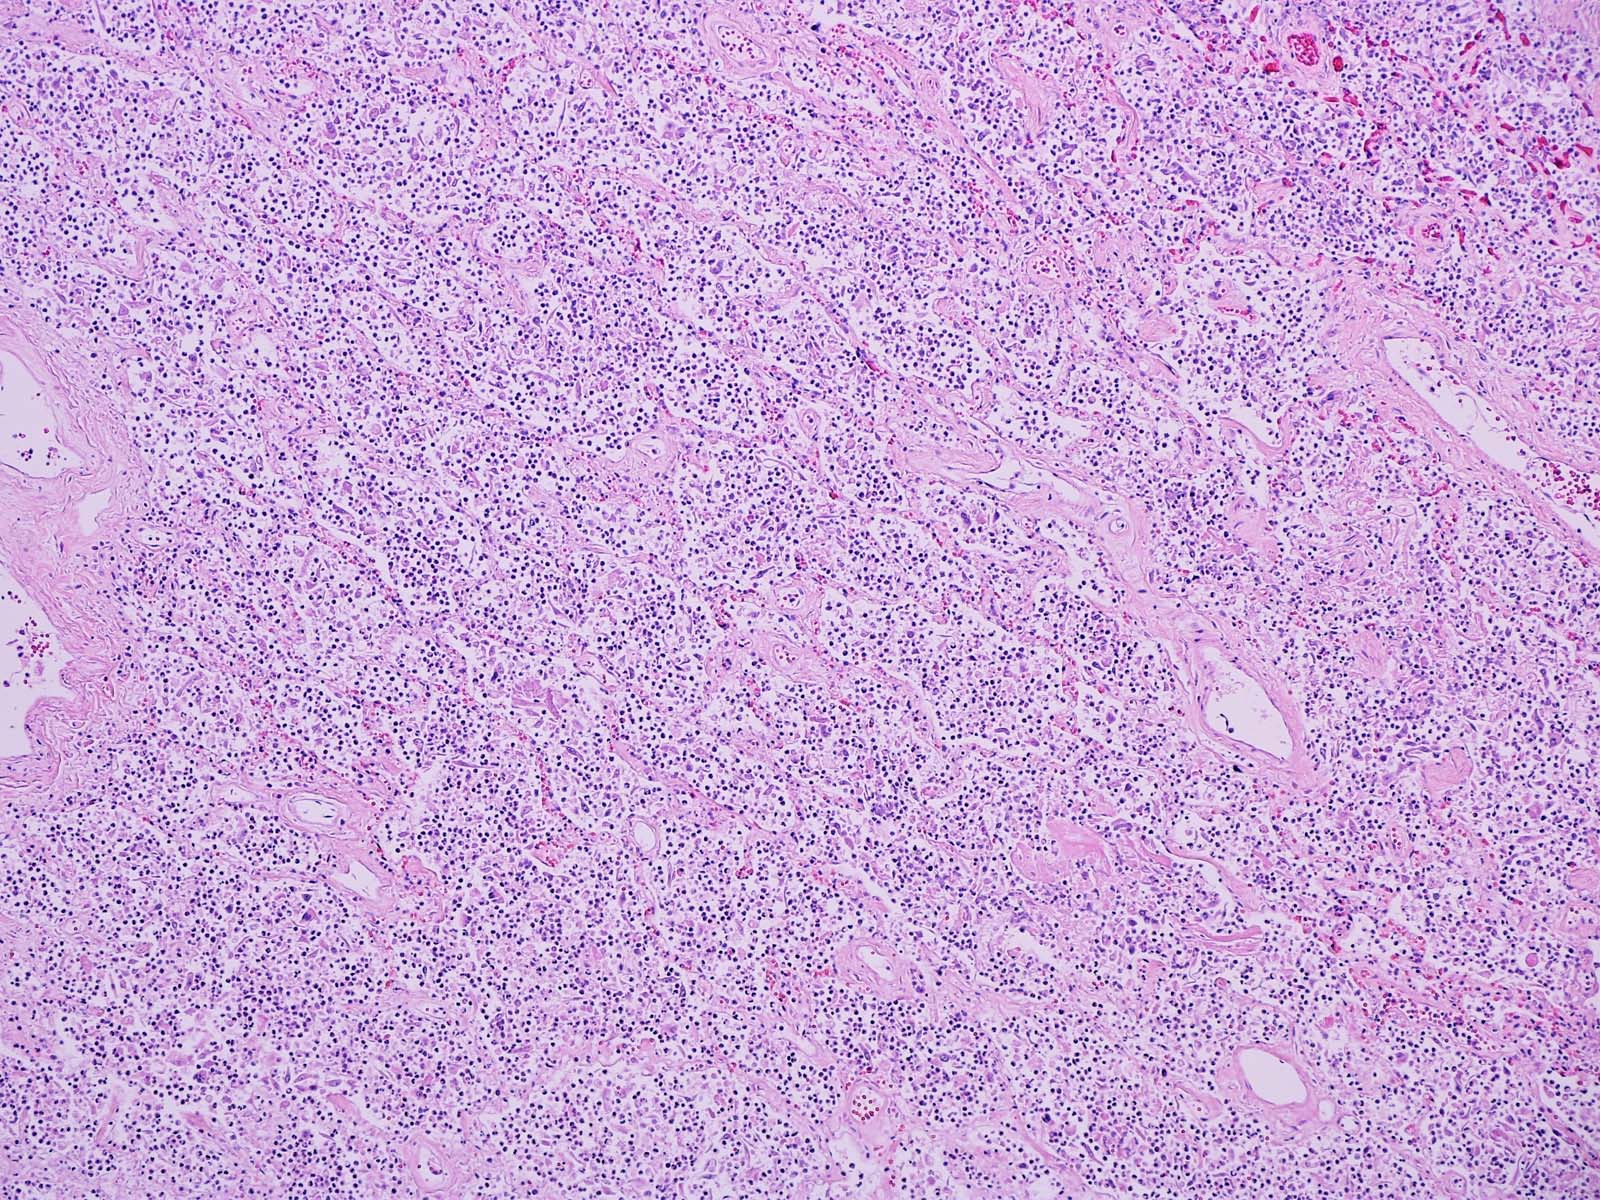

Microscopic (histologic) description

- Lobar pneumonia (Semin Diagn Pathol 2017;34:498):

- Uniform inflammatory infiltrate, the changes are at the same stage throughout the entire lobe

- Early stage: vascular engorgement, intra-alveolar fluid with few neutrophils and often bacterial colonies

- Massive confluent exudate with intra-alveolar neutrophils, red cells and fibrin, correlates with red hepatization on gross exam

- Progressive disintegration of red cells and the persistence of a fibrinosuppurative exudate, correlates with gray hepatization on gross exam

- Resolution phase: exudates converted to fibromyxoid masses rich in macrophages and fibroblasts

- Usually resolves with minimal fibrosis

- Pleuritis can be seen

- Bronchopneumonia:

- Most common pattern of pulmonary infection

- Different stages in the different areas

- Patchy intra-alveolar fibrinopurulent exudate with neutrophils

Microscopic (histologic) images

An 80 year old man presented with dyspnea, altered mental status and evidence of urinary tract infection. He was hospitalized in an intensive care unit for 2 weeks. The patient later developed fever, hypoxemia and new infiltrate on chest radiograph. An autopsy was performed and the lung showed the above histomorphology. What is the likely diagnosis?